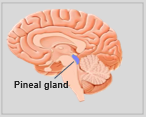

La neuroanatomie est la branche de l'anatomie qui étudie l'anatomie du système nerveux, c'est-à-dire la structure, la fonction et l'organisation du système nerveux.

Le système nerveux est l'un des systèmes les plus complexes du corps humain, et il comprend le cerveau, la moelle épinière, les nerfs périphériques et les ganglions nerveux. La neuroanatomie s'intéresse à la manière dont ces structures sont reliées les unes aux autres, comment les signaux sont transmis entre les cellules nerveuses, et comment les différentes parties du système nerveux travaillent ensemble pour contrôler les fonctions corporelles et cognitives. Les neuroanatomistes utilisent des techniques d'imagerie avancées, comme l'imagerie par résonance magnétique (IRM), la tomographie par émission de positons (TEP) et la microscopie pour visualiser les structures et les fonctions du système nerveux.